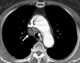

Squamous cell lung cancer

Non-small-cell lung carcinoma (NSCLC) is any type of epithelial lung cancer other than small-cell lung carcinoma (SCLC). NSCLC accounts for about 85% of all lung cancers. [Source: Wikipedia ]